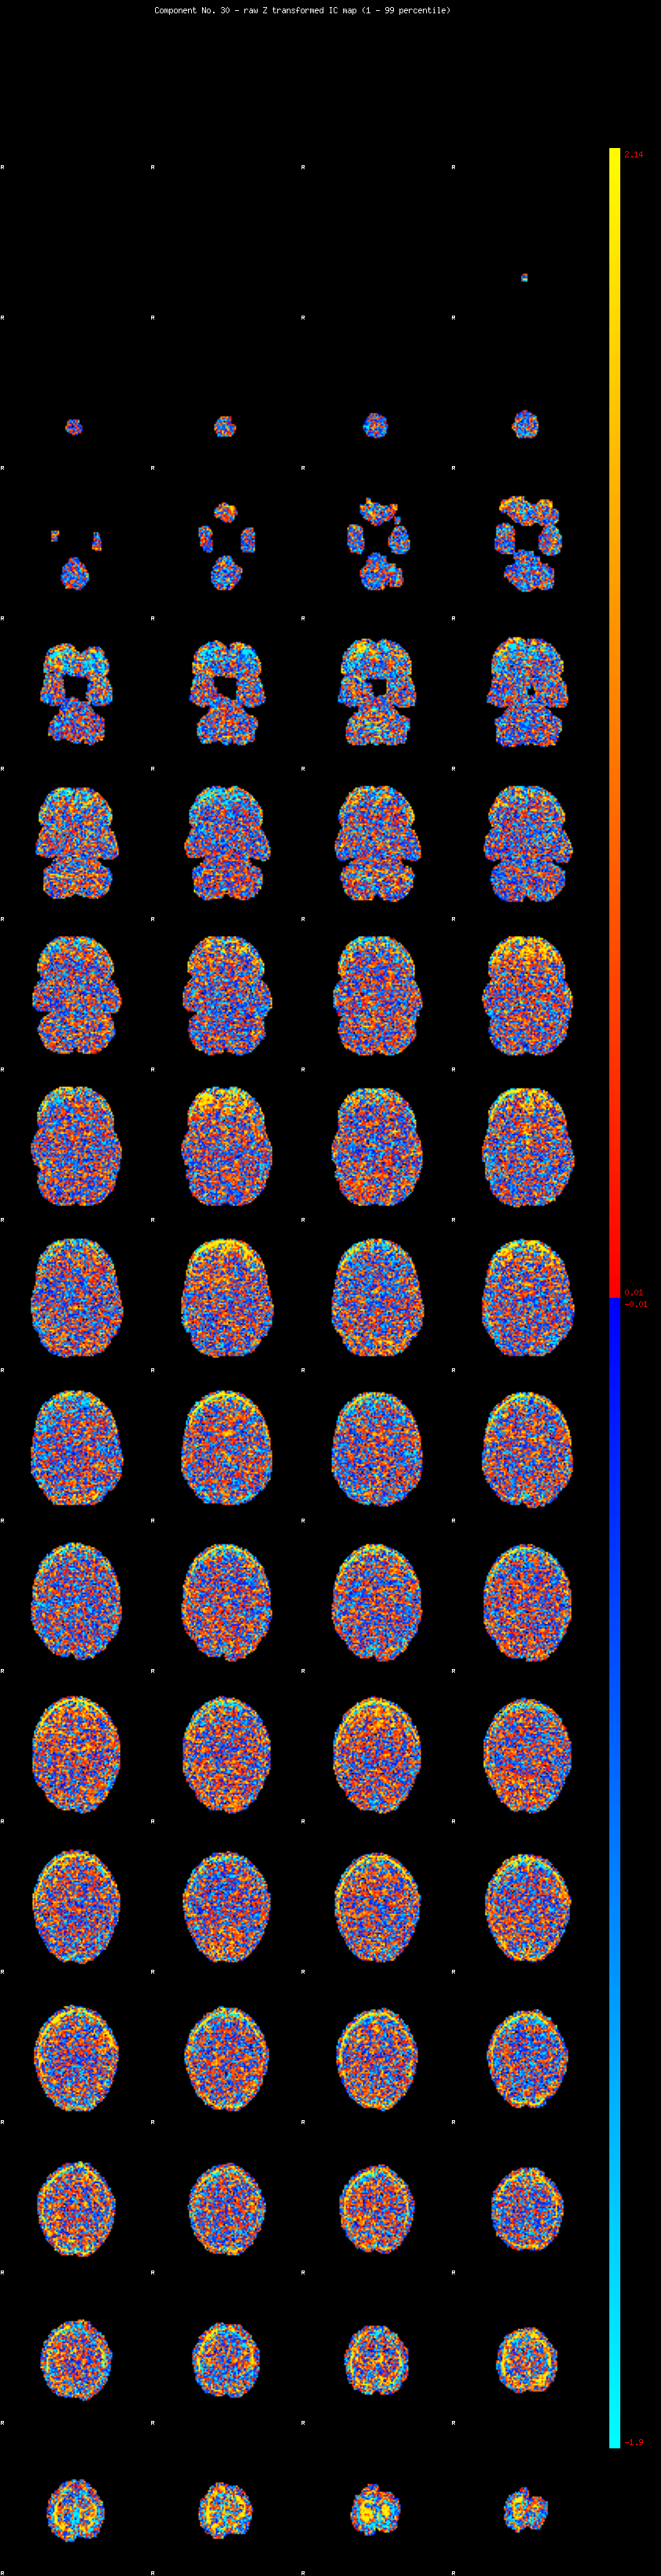

IC_30 Mixture Model fit

Means : -0.000000 2.582019 -2.602038

Vars : 1.000000 2.303348 0.987706

Prop. : 0.934410 0.045671 0.019919